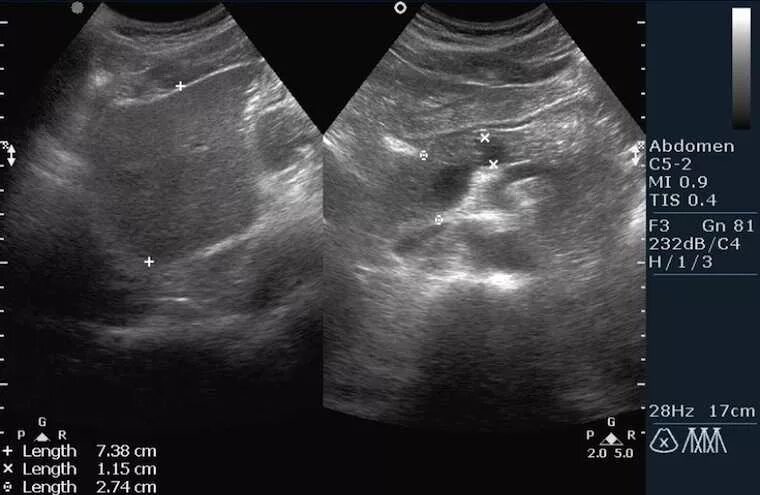

Поджелудочная диффузно неоднородная